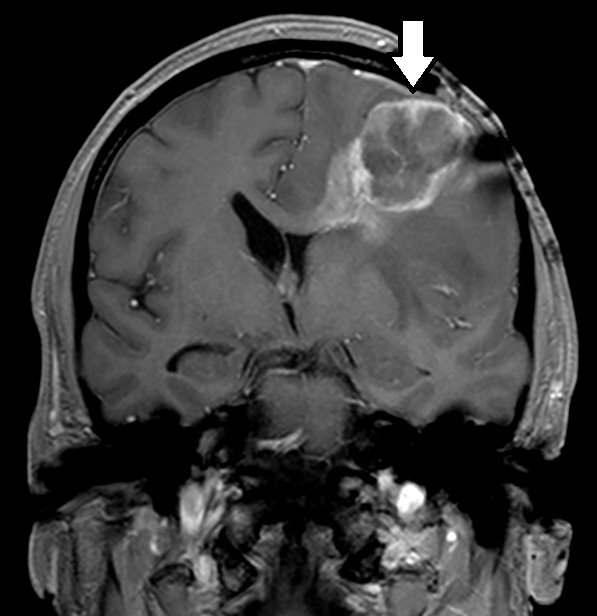

MRIは頭部の断層像で脳腫瘍や梗塞、出血がわかります。MRAは、血管のみ抽出した検査で、くも膜下出血、脳動脈瘤など脳内血管障害の発見に用います。

MRIではCT検査と同様、腫瘍の大きさや形、数などがわかります。また、MRAでは脳動脈瘤、脳梗塞、脳動静脈奇形、もやもや病、閉塞性動脈病変などの脳血管障害がわかります。脳ドックでは、くも膜下出血の原因となる脳動脈瘤のスクリーニング検査としてよく用いられています。